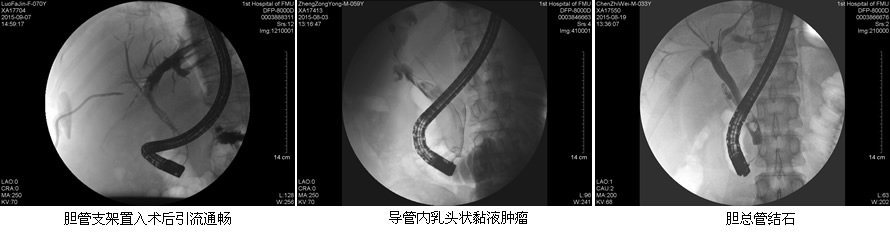

目前ERCP适应症主要包括:原因不明的阻塞性黄疸疑有肝外胆道梗阻者;疑有各种胆道疾病如结石、肿瘤、硬化性胆管炎等诊断不明者;疑有先天性胆道异常或胆囊术后症状再发者;胰腺疾病:胰腺肿瘤、慢性胰腺炎、胰腺囊肿等。在这50余例病例中,包含了内镜下乳头活检术、乳头括约肌切开取石术、胆管内支架引流术、鼻胆管引流术、“三镜”联合治疗胆总管结石等,患者术后无明显并发症发生,获得了良好的疗效,使我院ERCP诊疗技术进入一个崭新的时代。

在工作中,该团队始终坚持“用科研的态度对待每一例患者!”无论是小小的十二指肠乳头活检术,还是难度较大的胃毕Ⅱ术后乳头切开取石术,乃至肝门部高位胆管癌内支架置入术,“安全至上”的理念始终体现在每一位患者身上。无论简单还是复杂,ERCP团队的每一位成员,术前都严格评估适应症和禁忌症,术中规范操作,术后应按预案防治并发症,确保了每一例患者的安全。